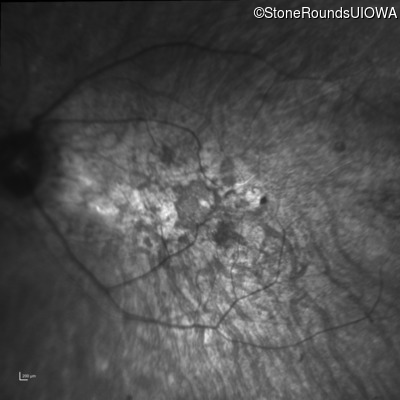

Optical Coherence Tomography - Left - 20/70 sc

Exemplar / OCT Stack

OCT Stack

Infrared Fundus Photograph - Left - 20/70 sc

Exemplar